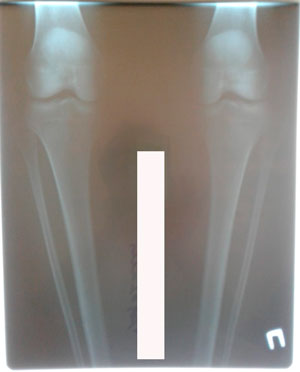

Исходник - 35 лет.

Дата операции - 10.03.2020

перед крутками